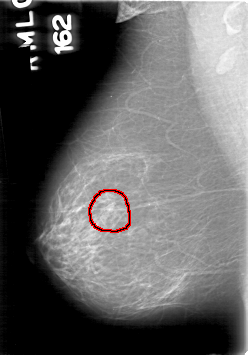

D_4094_1.LEFT_CC

RIGHT_MLO LINES 5311 PIXELS_PER_LINE 3706 BITS_PER_PIXEL 12 RESOLUTION 43.5 OVERLAY

FILE: D_4094_1.RIGHT_CC.OVERLAY

TOTAL_ABNORMALITIES 1

ABNORMALITY 1

LESION_TYPE MASS SHAPE ROUND MARGINS OBSCURED

ASSESSMENT 0

SUBTLETY 4

PATHOLOGY BENIGN

TOTAL_OUTLINES 1

BOUNDARY